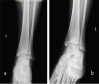

Figure 8

Fixation of the distal tibia with a Mesh Plate and eight screws.

Figure 9

Post-operative anteroposterior (a) and lateral (b) radiographs of the left distal tibia after excision of avascular necrosis, bone grafting, and fixation.

Figure 10

Anteroposterior (a) and lateral (b) radiographs 6-month postoperatively.